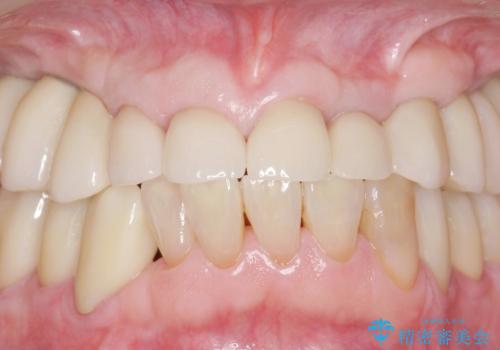

審美的な仕上がりと自然な咬み心地に喜んで頂けました。

治療前は口元を隠すようにお話しされていたのですが、治療後はそれもなくなり、満面の笑顔を見せて下さいました。

クラウンの種類:オールセラミッククラウン スタンダード